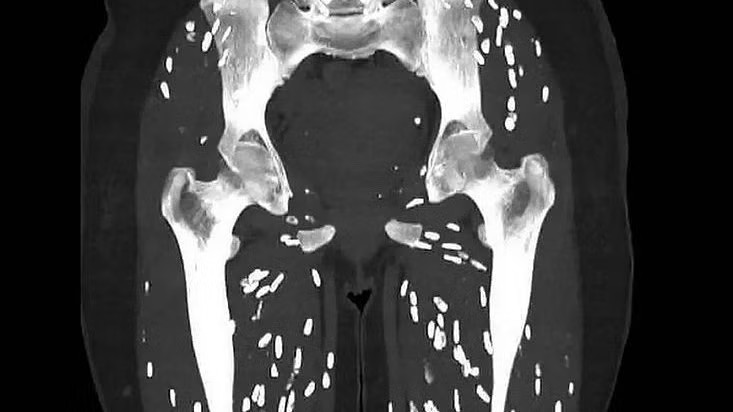

Tiến sĩ Ghali đăng hình CT chân của người bệnh kèm chú thích: "Đây là một trong những bản chụp đáng sợ nhất mà tôi từng thấy". Phim cho thấy sự hiện diện của bệnh sán dây do Taenia solium (sán dây lợn) gây ra.

“Người bệnh ăn phải nang sán trong thịt lợn nấu chưa chín. Sau vài tuần (khoảng 5-12 tuần), những nang sán đó phát triển trong đường tiêu hóa thành sán dây trưởng thành tiếp tục đẻ trứng. Tình trạng này được gọi là bệnh sán dây ruột”, Tiến sĩ Ghali giải thích.